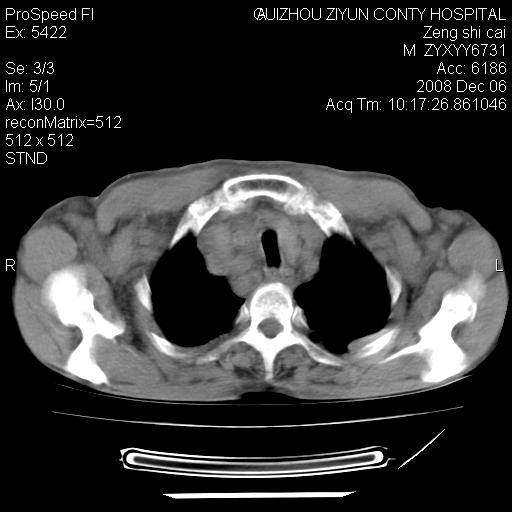

标题: CT16961:M、71岁,咳嗽半年,无血痰;胸片示右肺占位。 [打印本页]

标题: CT16961:M、71岁,咳嗽半年,无血痰;胸片示右肺占位。

右肺癌并纵隔淋巴结及胸膜转移可能性大

右肺癌并纵隔淋巴结及胸膜转移。建议气管镜

右肺纵隔型肺癌伴纵隔淋巴结及胸膜转移!

右肺纵隔型肺癌伴纵隔淋巴结转移!双侧胸水!

1)考虑右肺上叶纵隔型肺癌伴纵隔淋巴结转移。2)心包积液,双侧胸腔积液。

右肺癌并纵隔淋巴转移,腹膜后转移可能性大,两侧胸腔积液

右肺癌并纵隔淋巴结及胸膜心包转移,好多团团点点,看得有点想吐